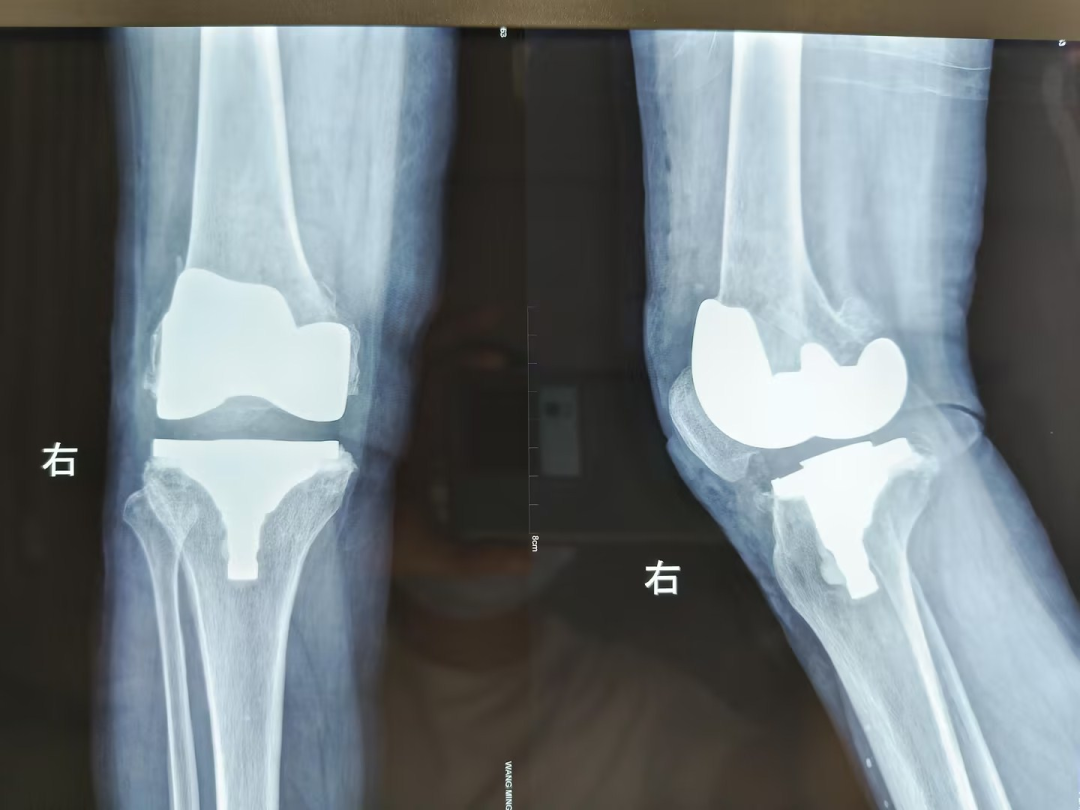

在创伤骨科住院后,经安勇主任医师团队诊断,王先生为双侧膝关节骨性关节炎,双侧膝关节内翻畸形。结合病史及影像学检查,考虑行双侧膝关节置换手术,因王先生左膝疼痛较右膝疼痛明显,所以先行左膝关节置换手术,术后10天,患者左膝疼痛减轻后,再行右膝膝关节置换手术。手术取得圆满成功,解除了王先生十余年的病痛。